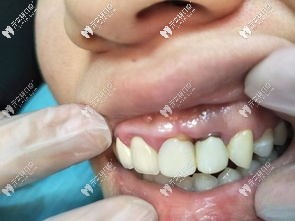

齲壞的上門牙

▲4顆齲壞的上門牙